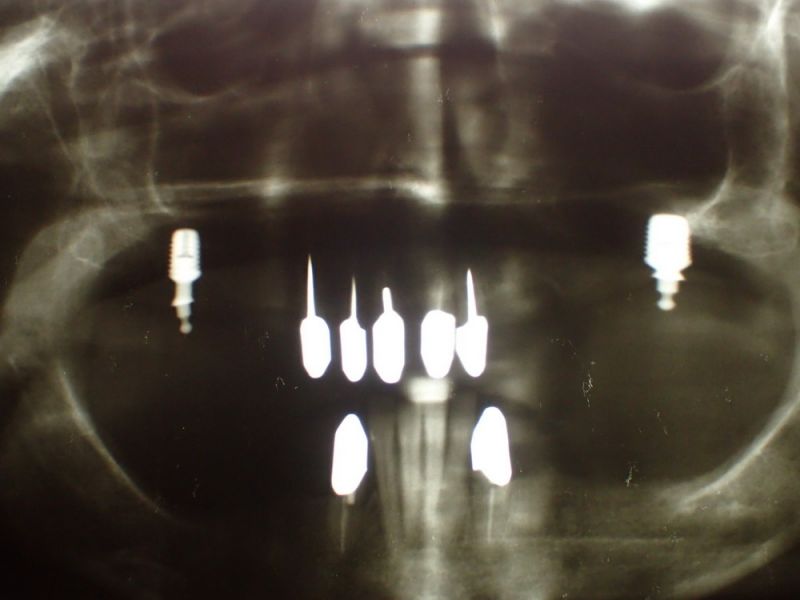

Vorhandene Teleksoparbeit, seit 15 Jahren im Munde der Patientin und aktuelles Übersichtsröntgenbild vor der Entfernung des Zahnes 33